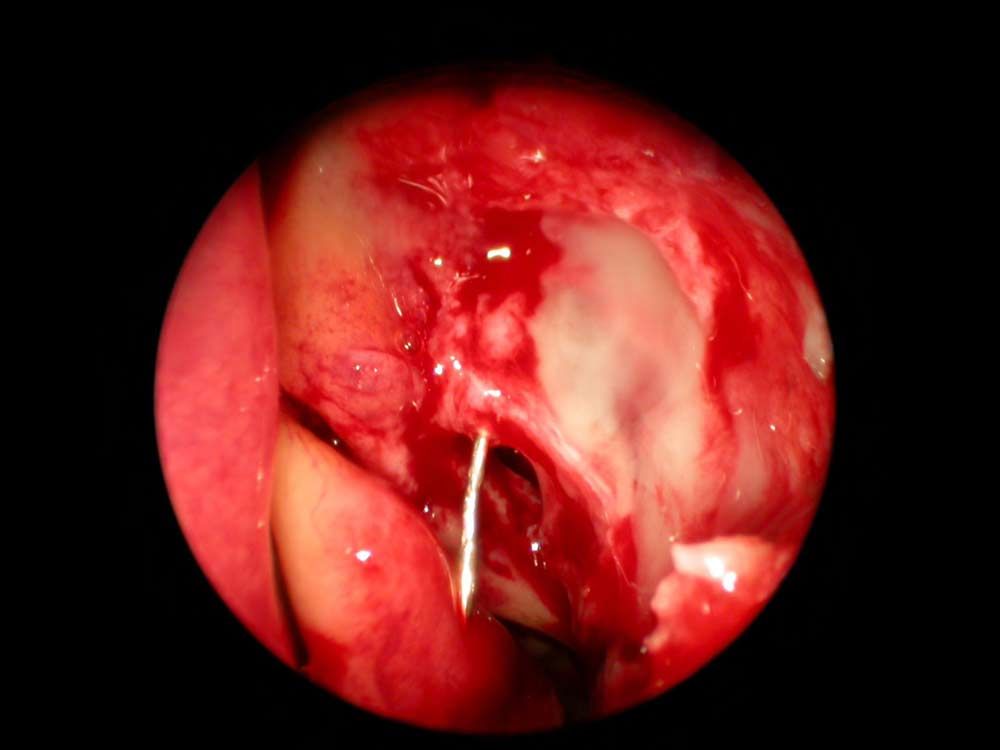

Tränenwegssonden in der Nase nach Eröffnen des Tränensacks

Rechts im Bild der linke Tränensack von innen in der Nase